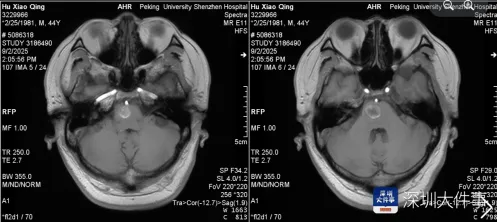

家人紧急将其送往医院,急诊检查结果让所有人揪心——头颅MRI显示,阿伟脑干桥脑右侧存在占位性病变,确诊为海绵状血管瘤并出血。

检查结果显示,其脑干桥脑右侧的海绵状血管瘤已破裂出血,随时可能危及生命。经过多学科精密规划和6小时的高难度手术,神经外科团队成功拆除这枚“生命中枢炸弹”,让阿伟重获新生。